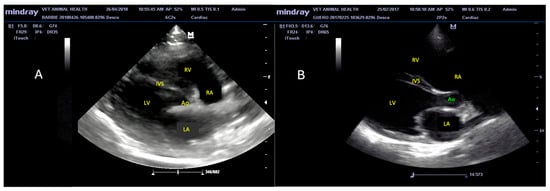

3.2. Echocardiographic Findings

3.3. M-Mode Ultrasonographic Findings